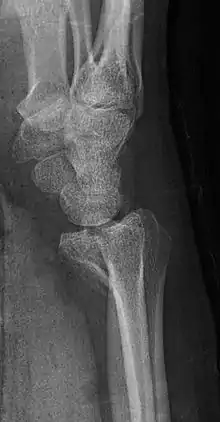

Barton's fracture

A Barton's fracture is a type of wrist injury where there is a broken bone associated with a dislocated bone in the wrist, typically occurring after falling on top of a bent wrist.[1] It is an intra-articular fracture of the distal radius with dislocation of the radiocarpal joint.[2]

There exist two types of Barton's fracture – dorsal[3] and palmar, the latter being more common. The Barton's fracture is caused by a fall on an extended and pronated wrist increasing carpal compression force on the dorsal rim. Intra-articular component distinguishes this fracture from a Smith's or a Colles' fracture. Treatment of this fracture is usually done by open reduction and internal fixation with a plate and screws, but occasionally the fracture can be treated conservatively.